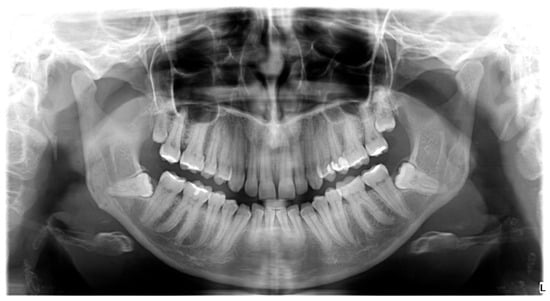

Impaction of four teeth was observed in the largest number of patients in the study group, whereas patients with two impacted teeth were the second most numerous subgroup (Figure 1).

Figure 1.

Impaction of four third molars on orthopantomogram (OPG).